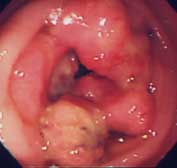

急性胃炎:

心窩部痛、食欲不振、吐き気を訴えて来院。内視鏡検査を施行すると、前庭部に線状のびらんを認め、急性胃炎の所見です。整形外科から処方された鎮痛剤が原因でした。抗潰瘍剤、粘膜保護剤の内服で症状は速やかに消失しました。